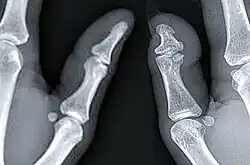

| X-ray of a regular thumb (left) and a thumb with brachydactyly type D (right) showing distal phalange brachyphalangy of said thumb. | |

Brachydactyly type D, also known as murderer's thumb,[3][1] stubbed thumb,[4][5] spoon thumb, power thumb or short thumb,[4][5] is a genetic trait recognised by a thumb being relatively short and round with an accompanying wider nail bed. The distal phalanx of such thumbs is approximately two-thirds the length of full-length thumbs. It is the most common type of shortness of digits (brachydactyly), affecting approximately 2% of the population. It is associated with the HOXD13 gene, located on chromosome 2q31.1.[6]

Brachydactyly type D is a skeletal condition that exhibits a “partial fusion or premature closing of the epiphysis with the distal phalanx of the thumb,” according to Goodman et alia (1965).[5] J.K. Breitenbecher (1923) found that the distal phalanges of short thumbs were one-half the length of full-length thumbs, while R.M. Stecher (1957) claimed that it is approximately two-thirds. The condition may be unilateral (affecting one thumb) or bilateral (affecting both).[5]